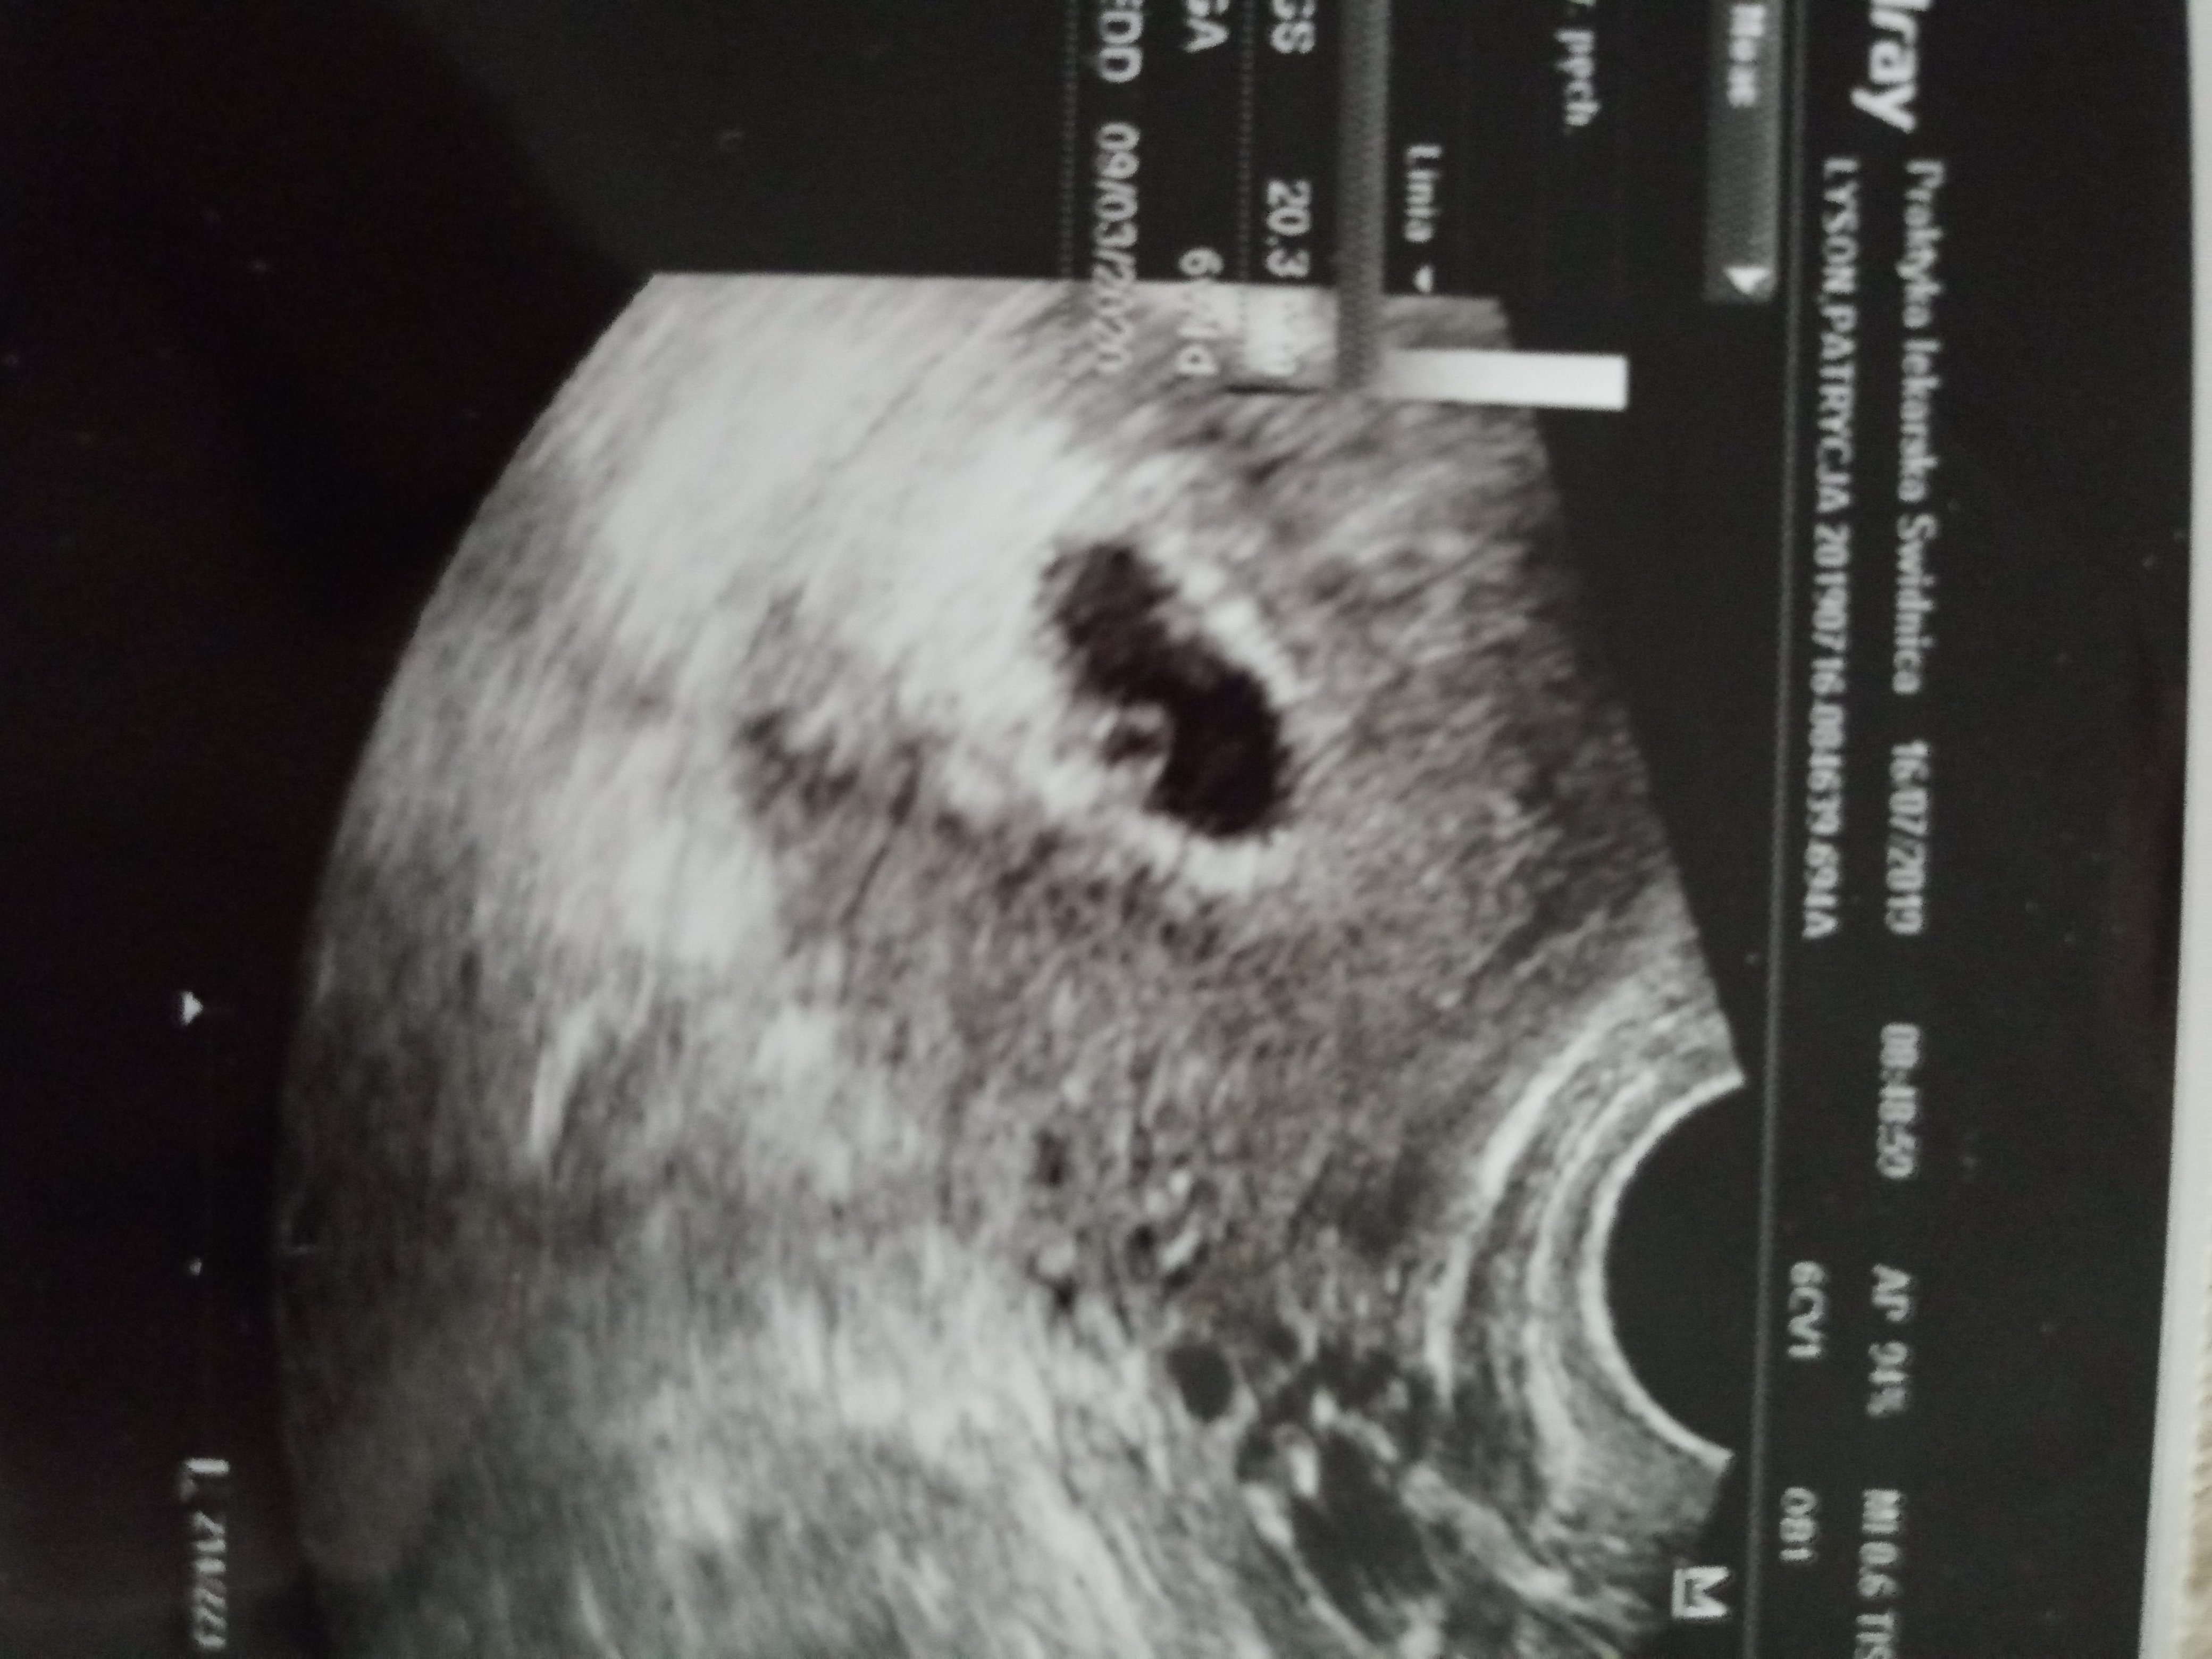

Teraz znowu jestem w ciąży, znalazłam dobrego lekarza z polecenia 1 USG po dwóch tygodniach od spóźniającej się miesiączki i wyrok ... Puste jajo płodowe .. lekarz dał mi tydzień. Po tygodni znów kontrola i znów ten sam wyrok, umówił mnie na drugi dzień na zabieg .. byłam w szoku wzięłam skierowanie i? Zaraz chwilę później pojechałam do lekarza który prowadził moja 1 ciążę .. nie powiedzualam mu o poprzedniej wizycie i czekałam na ten sam wyrok... Lekarz zrobił USG , od miesiączki minęło wtedy 7 tygodni ... Robi badanie i mówi że z USG wychodzi 5t2d widać ładny pęcherzyk i tyle, dał skierowanie na badania ciążowe i kazał przyjść za miesiąc.. zaczęłam go podpytywać czy to nie znaczy że coś się dzieje złego, a on do mnie że nie.. że czasem owulacja jest przesunięta i nie widzi nic niepokojącego ..

Dał mi nadzieję na to że za jakiś czas ujrzymy coś na USG! Ale ciągle dręczy mnie tamta diagnoza i pośpiech poprzedniego lekarza ... Może faktycznie tą ciąża jest młodsza? Czy któraś z Was spotkała się z czymś podobnym?

• 67925805_946338649045807_3594380897920483328_n.jpg

67925805_946338649045807_3594380897920483328_n.jpg

184,4 KB · Wyświetleń: 1 700